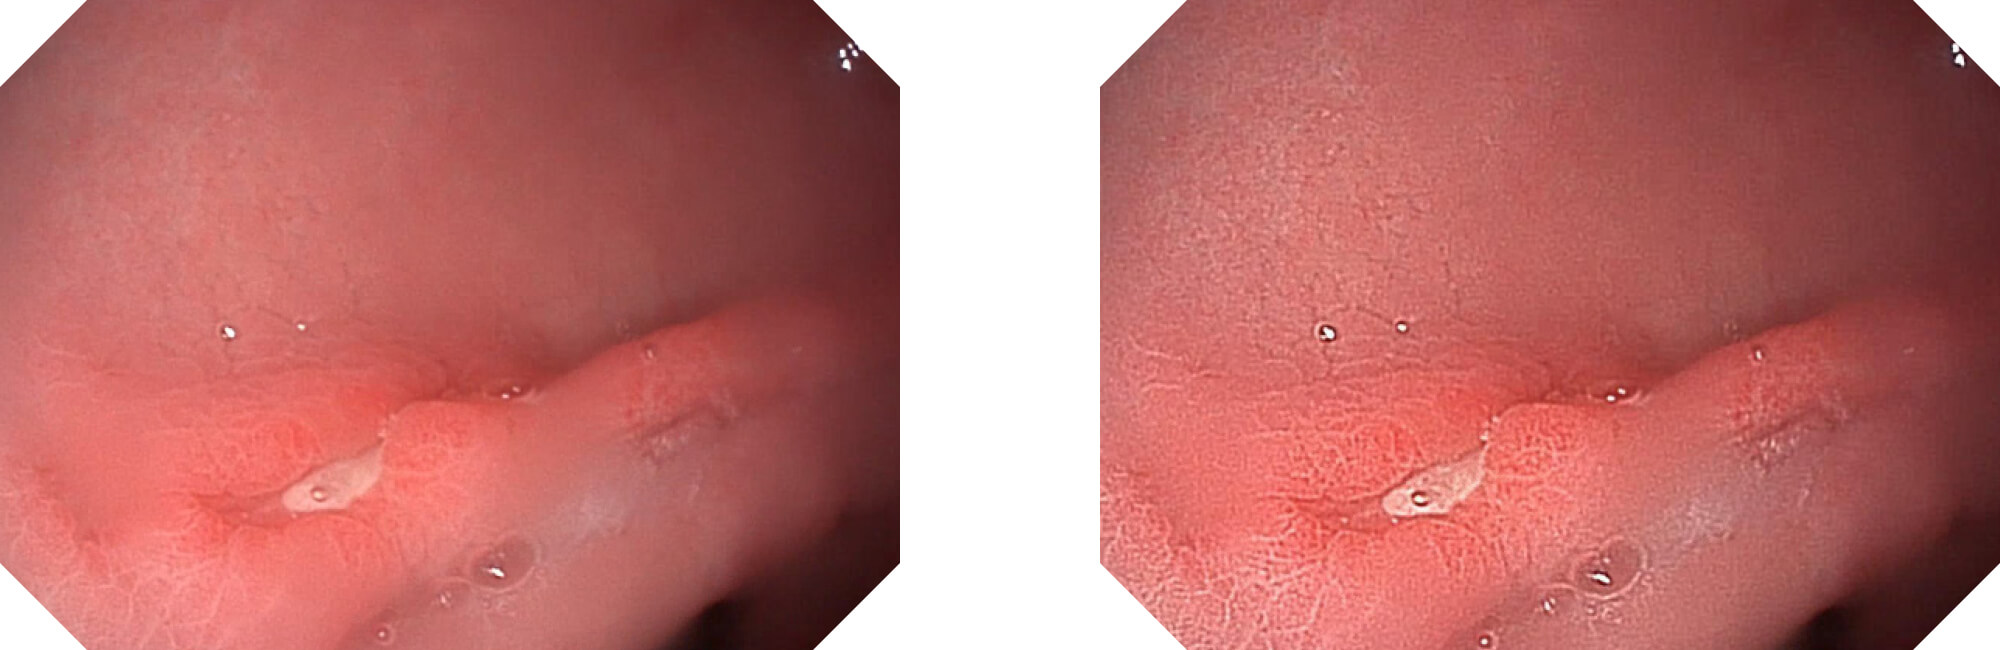

高清数字信号结合构造强调和色彩增强,多重图像处理技术能让每一个图像都清晰可见。

电子放大

(Versatile Intelligent Staining Technology)

利用了血红蛋白在不同波长吸收下系数不同的原理,设计的一种光学域滤波和数字域滤波结合的染色技术,既保证了图像亮度,又可增强黏膜血管的对比度,充分凸显早期病变的细微结构变化,为临床疾病的观察诊断提供更丰富的参考信息。